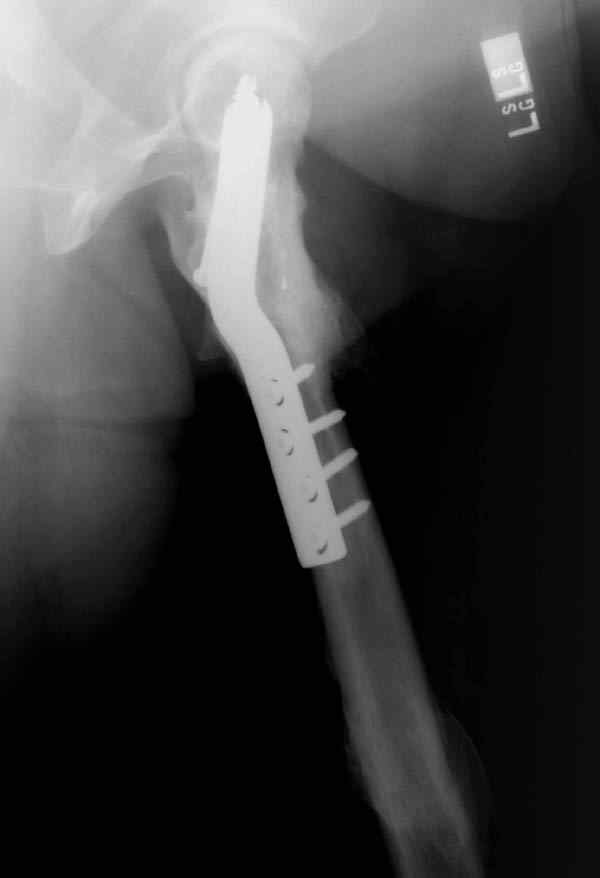

Ошибки случаются, когда игнорируются правила обследования больных с переломом бедра. Часто, когда "экономят" рентген пленки и снимают без надлежащих захватов сустава.

Одним из "золотых" правил при лечении переломов бедра в обязательном порядке до операции необходимо убедиться в отсутствии или наличии перелома шейки.

Отдельный снимок шейки или ЭОП является стандартом обследования. Все сомнительные рентген снимки проверяются тщательно дополнительными срезами КТ.

Из-за опасности вторичного смещения переломов "без смещения" во время интрамедуллярных манипуляций, особенно при ретроградном введении, необходимо каждый случай протоколировать с описанием состояния шейки после операции.

А не опорная болтающаяся конечность с большим рычагом усложнит состояние перелома шейки и поэтому ипсилатеральные переломы, тем более ятрогенные, очень часто осложняются двойными ложными суставами.